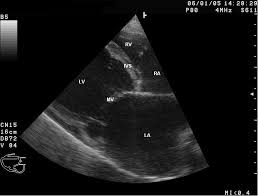

Joeristanti Soelistyaningroem, Iswanto PratanuStenosis yang signifikan pada Left Main Coronary Artery (LMCA) pertama kali dideskripsikan oleh Herrick (1912) , prevalensinya sekitar 2,5% - 10% pada penderita penyakit arteri koroner, dan sekitar 4%-6% ditemukan pada penderita yang sedang dilakukan angiografi koroner. Kondisi ini merupakan resiko tinggi , dengan angka mortalitas 5 tahun sebesar 42% jika hanya diberikan pengobatan medikamentosa. Angka morbiditas dan mortalitas ini tergantung dari beberapa faktor, termasuk beratnya stenosis LMCA, serta kondisi dari arteri koroner lainnya, yaitu Right Coronary Artery (RCA), left dominance, dan fungsi ventrikel kiri (LV) 1,2

Guideline terbaru merekomendasikan Coronary artery Bypass Grafting (CABG) sebagai terapi standar pada penderita stenosis LMCA. Karena selain mempunyai angka harapan hidup yang lebih bagus, beberapa penderita stenosis LMCA juga mempunyai multi-vessel coronary artery disease dimana revaskularisasi koroner dengan CABG mempunyai beberapa keuntungan.2,3,4

Meskipun teknik CABG yang semakin berkembang, iskemia miokard paska operasi masih merupakan problem yang penting, terjadi pada 3%-5% penderita post CABG. Oklusi graft atau trombosis merupakan penyebab tersering terjadinya iskemia ini, dan mempunyai angka morbiditas dan mortalitas yang cukup signifikan. Dilaporkan rata-rata angka mortalitas graft failure sekitar 14,5%- 21,7 %. Dimana arteri radialis graft mempunyai resiko tinggi terjadinya oklusi maupun severe flow limiting disease. Pemeriksaan angiografi koroner berguna untuk menegakkan diagnosa, mengetahui penyebab dari graft failure, serta menentukan tindakan selanjutnya. Penderita dengan graft failure akibat proses patologis dapat dilakukan PCI pada native coronary artery dengan aman